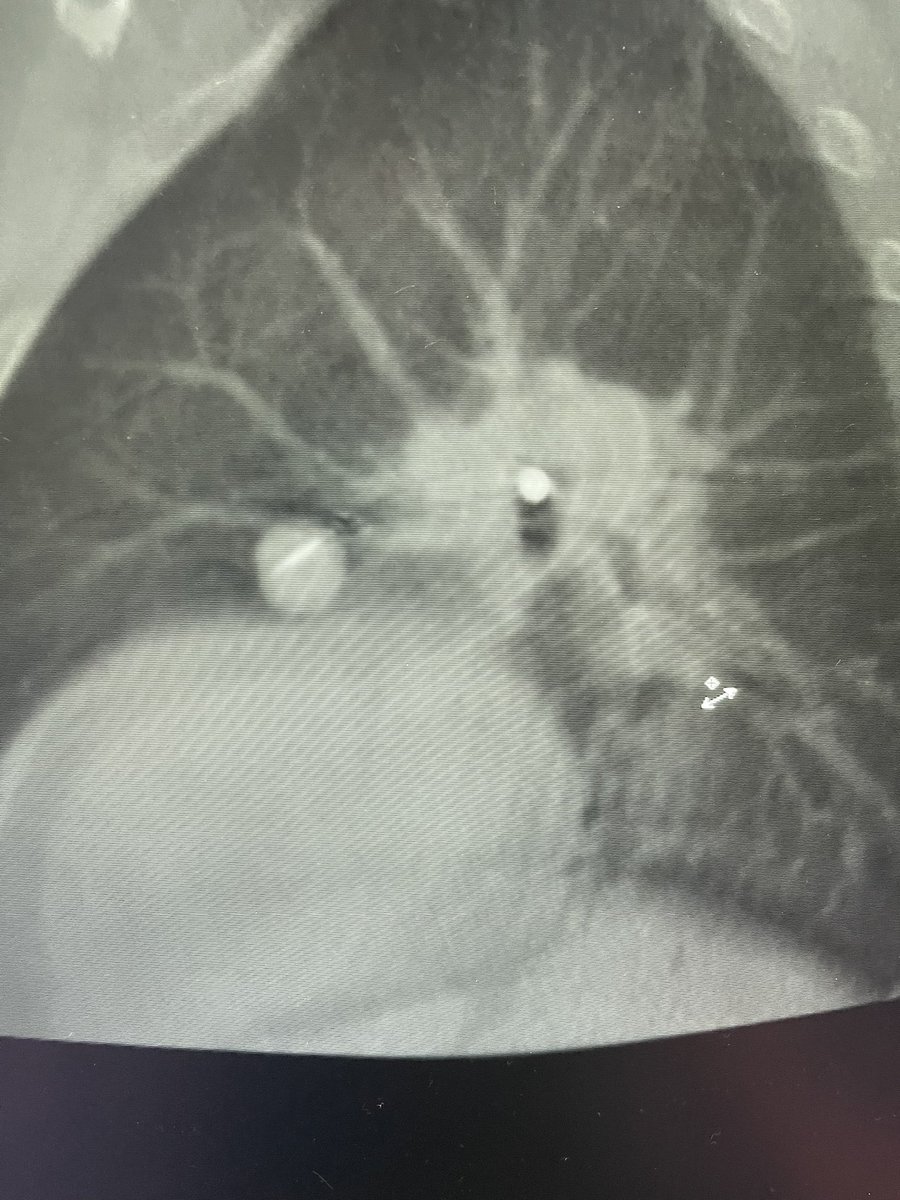

Bhadra & Condra CBCT Bronchoscopy

If you don't like the road you are on, pave a new one: Cone Beam CT Bronchoscopy.